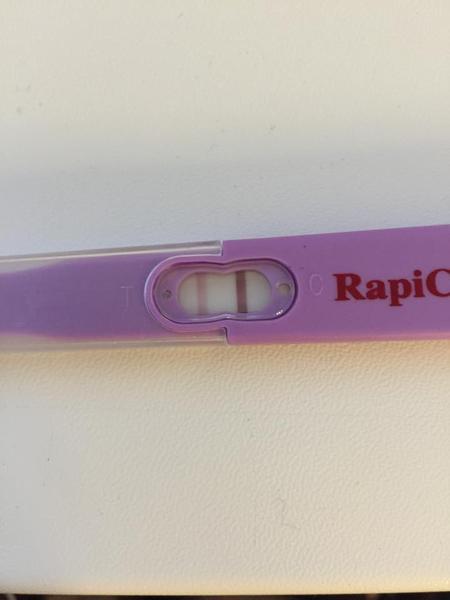

Chcela by som sa s vami podelit o moje testiky, v pondelok som davala foto mojho ´´dušíka´´ ktorý už vtedy nebol duchom, postupne silneli takto...avšak včera rano som sa zobudila na obrovsku bolest podbruska zbehla som na gyndu, kde hcg 115 na sone este nic, ale na lavom vajecniku utvar velkosti 4cm, mozne mimonaternicove tehitenstvo? s 3ma prizmurenymi ocami ma pustili domov s tym,ze v sobotu musim prist na dlasie hcg,ktore ak bude viac ako dvojnasobok sme v suchu...predpokladam ze ten utvar bola iba cysta a tie boli z jej prasknutia...teraz som uz fajn 🙂 a dnes som si spravila pre istotu dalsi test, a on silnie, takze myslim ze to MMT mozme vylucit 🙂 len pekne pozitivne! ale viac uvidime zajtra.